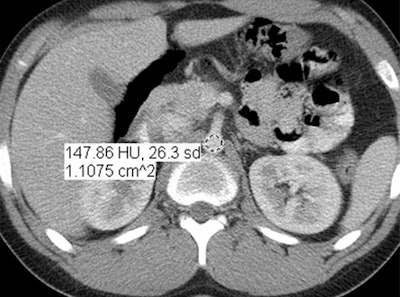

Images are of a 17-year-old boy with a history of Hodgkin's disease. Reduced-dose MBIR image (above), reduced-dose 100% ASIR image (below), reduced-dose filtered back projection image (third from top), and comparison standard-dose 30% ASIR image (bottom), all with a region of interest in the abdominal aorta for objective noise measurement. The reduced-dose MBIR image has significantly less noise compared with other reduced-dose and standard-dose reconstructions. Images republished with permission of RSNA from 10.1148/radiol.13130362, October 3, 2013.

In an objective evaluation, reduced-dose MBIR images had decreased image noise compared with standard-dose 30% ASIR images (for example, 12.7 HU versus 19.4 HU in the aorta, respectively, and 8.7 HU versus 14.2 HU in the liver).